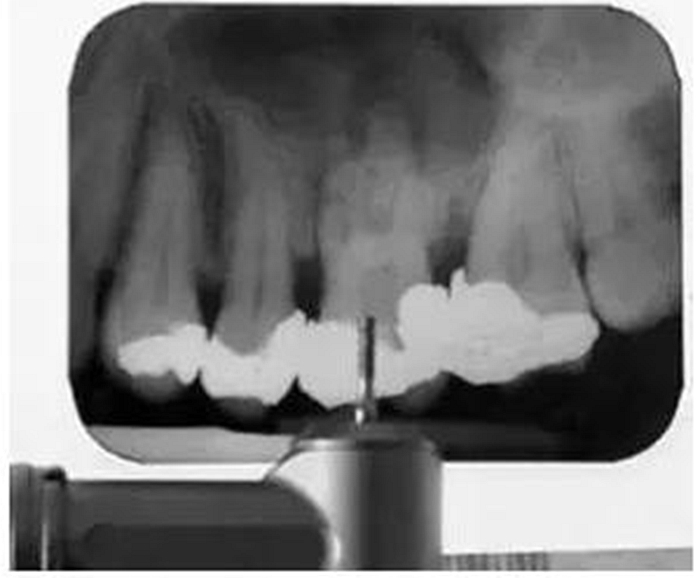

為了確保實(shí)現(xiàn)滿意的治療效果,在治療中要不斷確認(rèn)工作長度和充填質(zhì)量。在備樁或者進(jìn)行鈣化根管的根管治療時(shí),要拍攝根尖X線片以確保鉆或根管銼的方向是正確的(圖4)。這可以有效地防止治療失誤,如不必要的髓室底或者側(cè)壁穿孔。